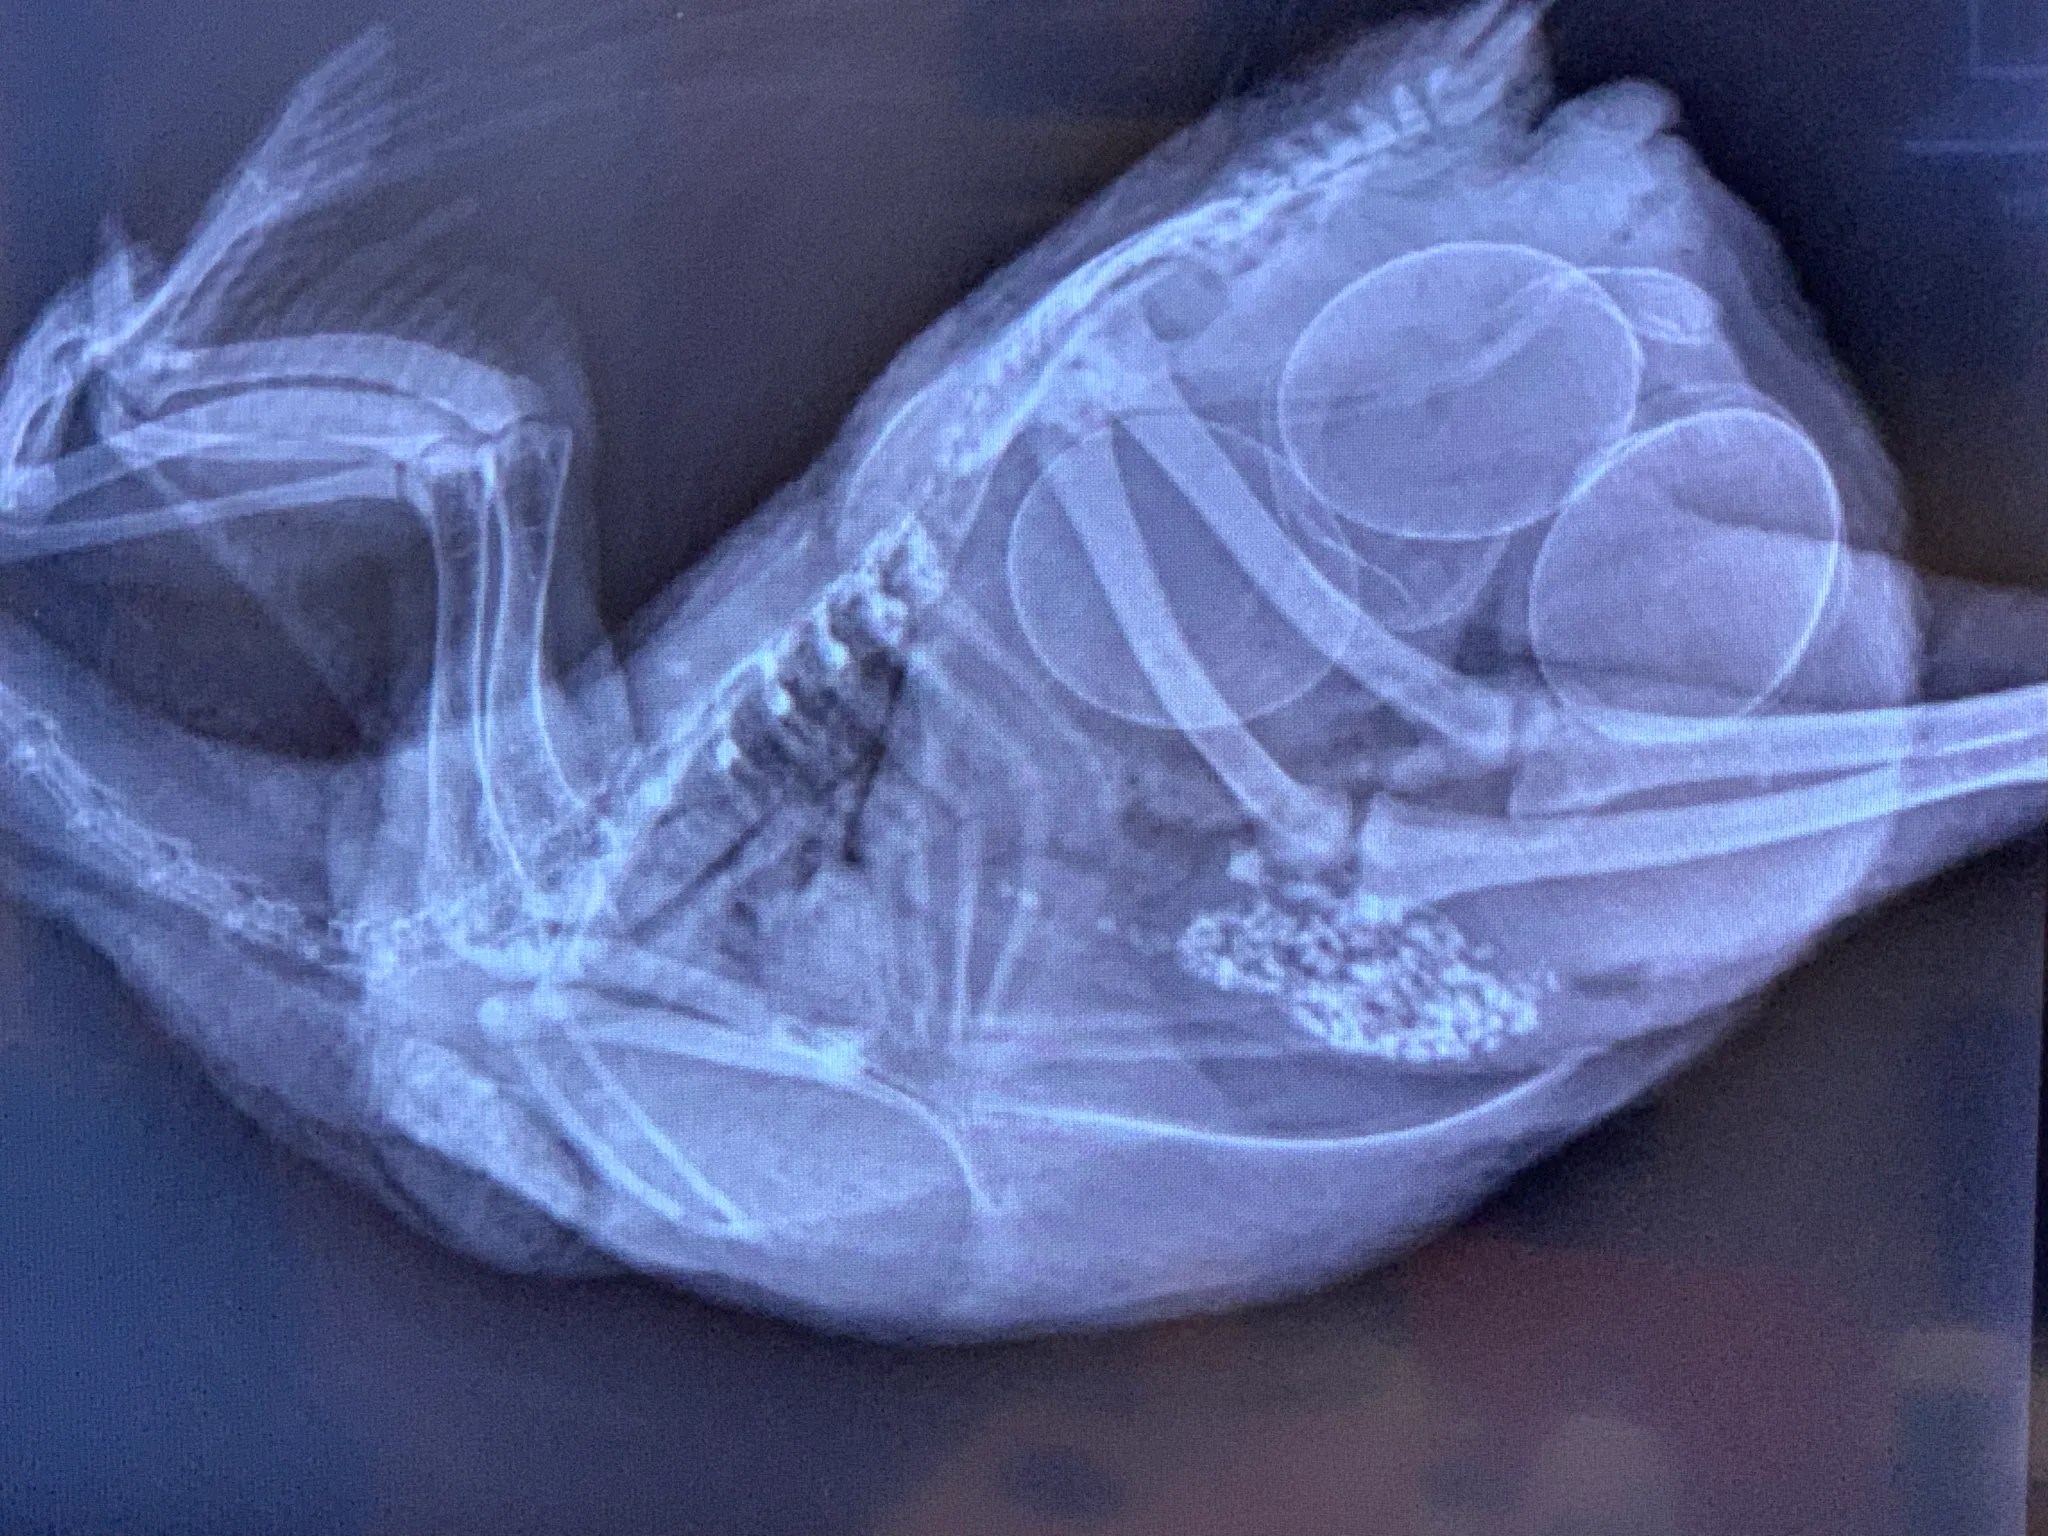

Once your hens reach point of lay, the left ovary (the right ovary is usually non-functional in most birds) will begin producing ova (yolks). They are passed to the infundibulum (oviduct) which, in normal egg production, will begin transporting them through the rest of the reproductive tract until they are eventually laid as fully-formed eggs. In a hen with EYP, the yolk is not caught by the infundibulum, but is instead released into the coelomic cavity.

EYP is inflammation in the peritoneum (tissue covering the inside of the abdomen and most organs) caused by the presence of yolk from a ruptured egg or a retained egg in the oviduct. The yolk may result in only mild inflammation and be absorbed by the peritoneum. Unfortunately the yolk is also a medium for bacteria, which can lead to infection such as E. coli or Staphylococcus.

Some of you may have heard the term ‘lash egg, which is a bit of a misnomer because technically it’s not an egg. The correct name is salpingitis, an inflammation of the oviduct caused by an infection, which occurs in various species including both chickens and people.

It’s a common condition in poultry, especially among commercial-farmed birds, who lay large numbers of eggs. High-producing hens tend to have more relaxed egg laying muscles, which may allow fecal bacteria to migrate up the oviduct. Or sometimes it’s a result of respiratory infections that move down into the oviduct. Salpingitis is often associated with Mycoplasma and bacteria like E.coli and Salmonella.

Some of the symptoms are so generalized they could be many things: lethargy, loss of appetite, ruffled feathers, yellow poop or respiratory illness. An affected hen will eventually lay fewer eggs or stop laying altogether. Other typical signs include distended abdomen and laying soft or wrinkled eggs.

An early infection might have been the result of damage from egg binding. The two conditions share symptoms such as standing upright like a penguin and straining as if trying to lay an egg.